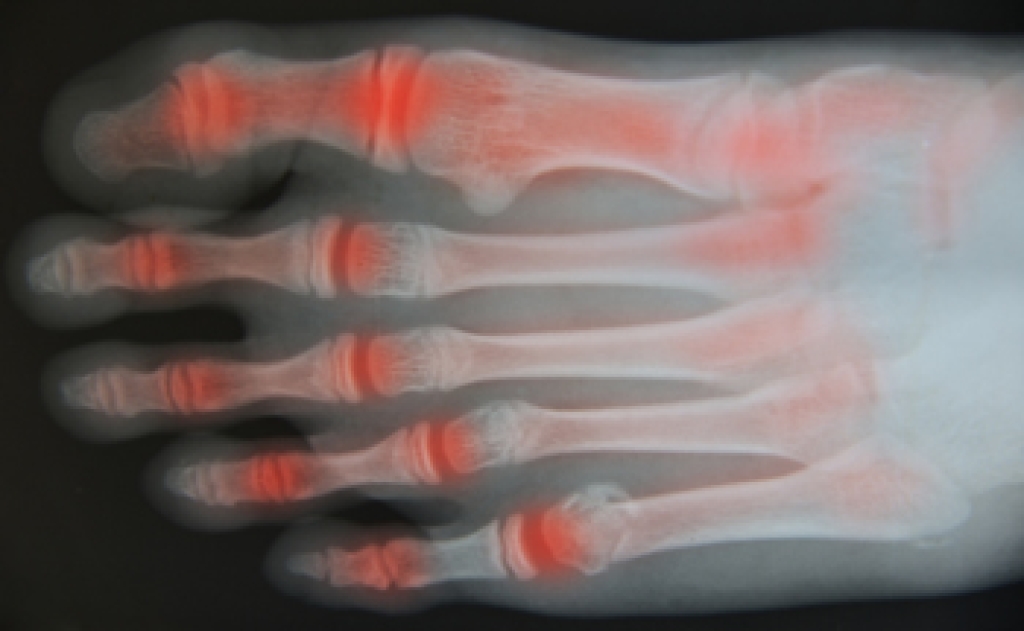

Arthritis, defined as joint inflammation, can lead to stiffness, swelling, and pain in affected joints. Among the 100 or more types of arthritis, studies have shown that three significantly impact the foot and ankle. Osteoarthritis, the most common, stems from joint cartilage wear and tear over time. Rheumatoid arthritis, or RA, is an autoimmune disease, that affects joints throughout the body, with women being twice as susceptible. RA involves the immune system attacking and damaging the cartilage. Post-traumatic arthritis, akin to osteoarthritis, can emerge years after fractures or injuries. Gout, another inflammatory condition, arises from uric acid crystal deposits that are near or within the connective tissue of the joints and is particularly common in the big toe. Psoriatic arthritis can produce symptoms that are similar to RA and is linked to psoriasis, a skin disorder causing scaling and flakiness. Understanding these types of arthritis can empower individuals to manage their foot health amidst arthritis challenges. If you believe you have developed a form of arthritis that is affecting your feet or ankles, it is suggested that you consult a podiatrist.

Arthritis is a joint disorder that involves the inflammation of different joints in your body, such as those in your feet. Arthritis is often caused by a degenerative joint disease and causes mild to severe pain in all affected areas. In addition to this, swelling and stiffness in the affected joints can also be a common symptom of arthritis.